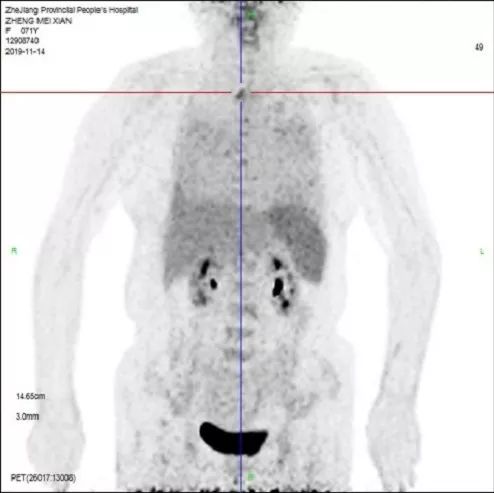

予完善骨髓穿刺+活检,骨髓涂片提示反应性骨髓象。行PET-CT:肝脏饱满,脾脏肿大,FDG代谢均增高;所示全身骨FDG代谢不均匀增高;双肺弥漫性网格样、条片状、斑片样密度增高影,FDG代谢增高;首先考虑炎性病变,需鉴诊合并血液系统疾病(图5)。

图5 PET-CT检查